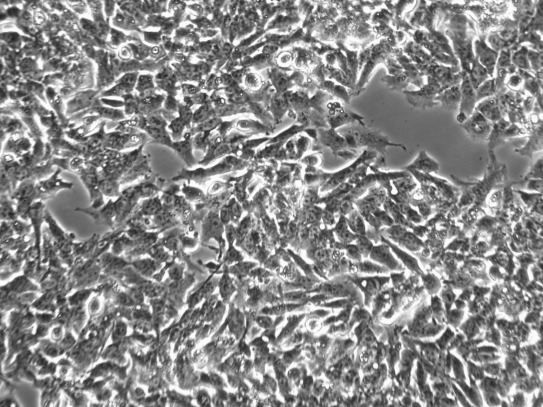

Hepg2人肝癌细胞

Hep G2细胞具有上皮样形态,最初附着在细胞的小块中,许多簇仍处于悬浮状态。几天后,生长将从粘附的细胞集落向外延伸。偶尔,细胞会堆积在粘附的集落上,形成多层外观,这对该细胞系来说并不罕见。是一种粘附细胞系。然而,一些细胞培养物比其他细胞培养物需要更长的时间才能附着。在从冷冻保存中恢复的第一周,培养物中的漂浮细胞是正常的。如果存在大量漂浮物,特别是在生长的第一周,请在前3天保持不受干扰。如果仍然有很多漂浮物,用台盼蓝检查生存能力。不要丢弃漂浮的细胞,当每2或3天喂入新鲜培养基时,应通过温和离心将其保留并添加回粘附群体中。

hepg2细胞图片